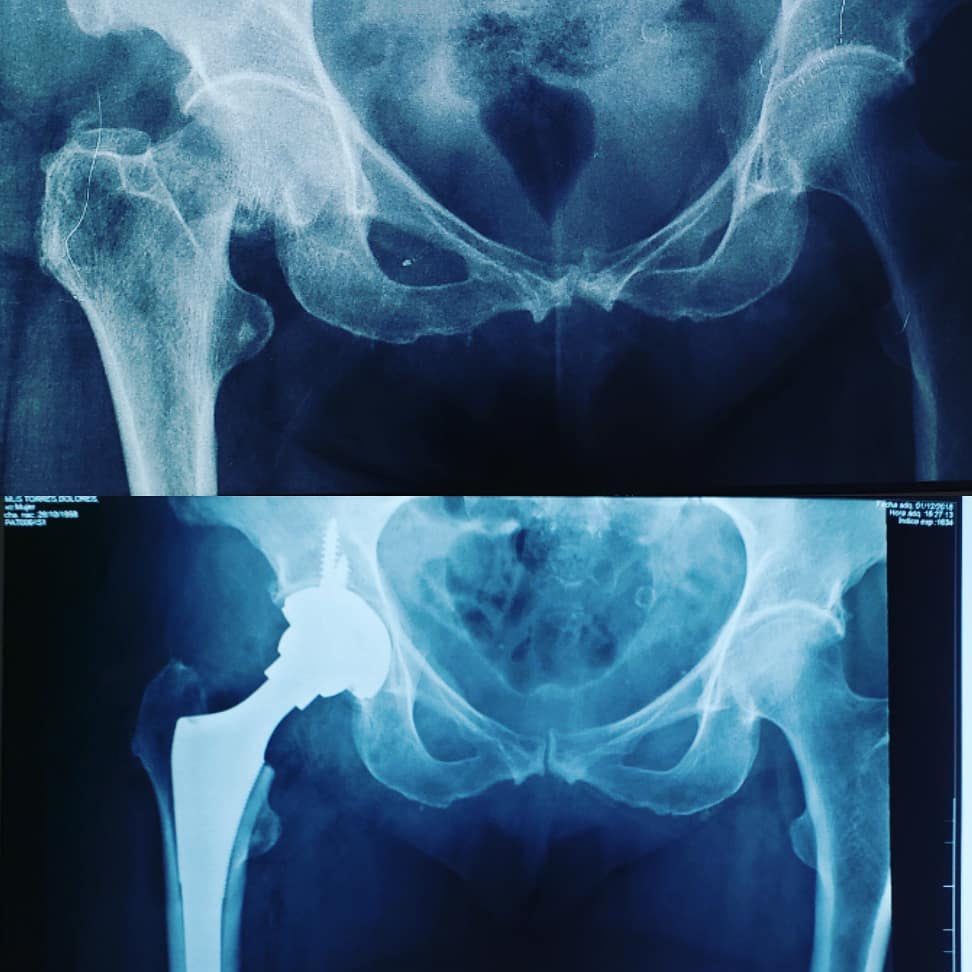

Desgaste articular

Se produce cuando el cartílago protector que amortigua los extremos de los huesos se desgasta con el tiempo. Aunque la osteoartritis puede dañar cualquier articulación, el trastorno afecta más comúnmente a las articulaciones de las manos, las rodillas, las caderas y la columna vertebral.

- Se maneja con medicamentos, terapia fisica, disminucion de peso.

- Reemplazo articular

Reemplazo articular

- Cuando se presenta una artrosis severa, que impide el movimiento y el dolor no deja vivir a los pacientes disminuyendo su calidad de vida se decide por el reemplazo articular.

- La artroplastia total recobra la movilidad y disminuye el dolor por desgaste articular severo.

- Una valoracion adecuada determina el momento adecuado para someterte a cirugia.